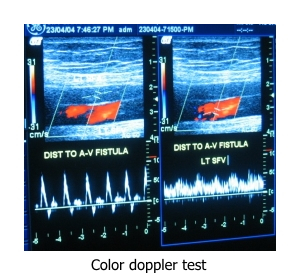

Color Doppler

Color Doppler/Ultrasound of vein: Color Doppler test helps in the diagnosis of varicose veins, deep vein thrombosis (DVT).

Color Doppler/Ultrasound of peripheral arteries: This is a basic test to confirm arterial blood supply to the peripheral organs like upper and lower limbs.

Dialysis access evaluation ultrasound: This ultrasound helps in evaluating the diameter and condition of veins of upper limb which are commonly used for dialysis access fistula.